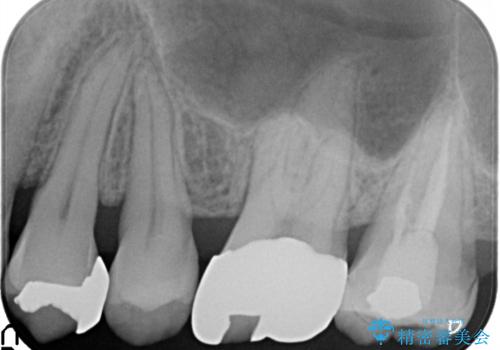

- 矯正の治療後に目立つ金歯を白くしたいとのことで治療することとなりました。

左上の奥歯に大きな金歯と、その後ろの歯が矯正治療用の仮歯が装着されていました。

これらの歯にオールセラミッククラウンを装着することとなりました。